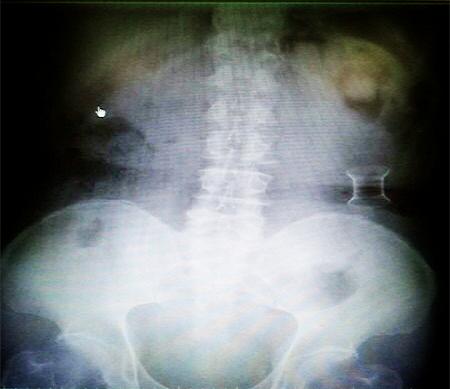

受試患者在結腸端端吻合術中,使用我司新研制產(chǎn)品達到了理想的預期效果?;颊咝g后7天、14天X光片顯影,可降解腸道支架均能按研制設計的預期時間節(jié)點保持應有強度,術后21天X光片顯示可降解腸道支架已完全破碎,并排出體外。在整個試驗過程中,病患無任何不良反映,耐受良好。